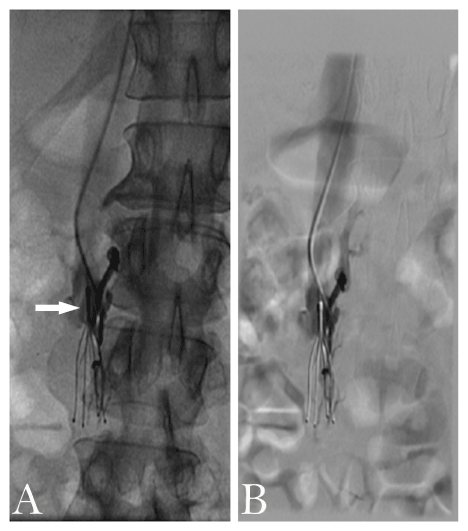

Figure 2. Occluded IVC filter. A and B depict the inferior vena cava filter thrombosed using digital subtraction angiography. Arrow: site of thrombosis.